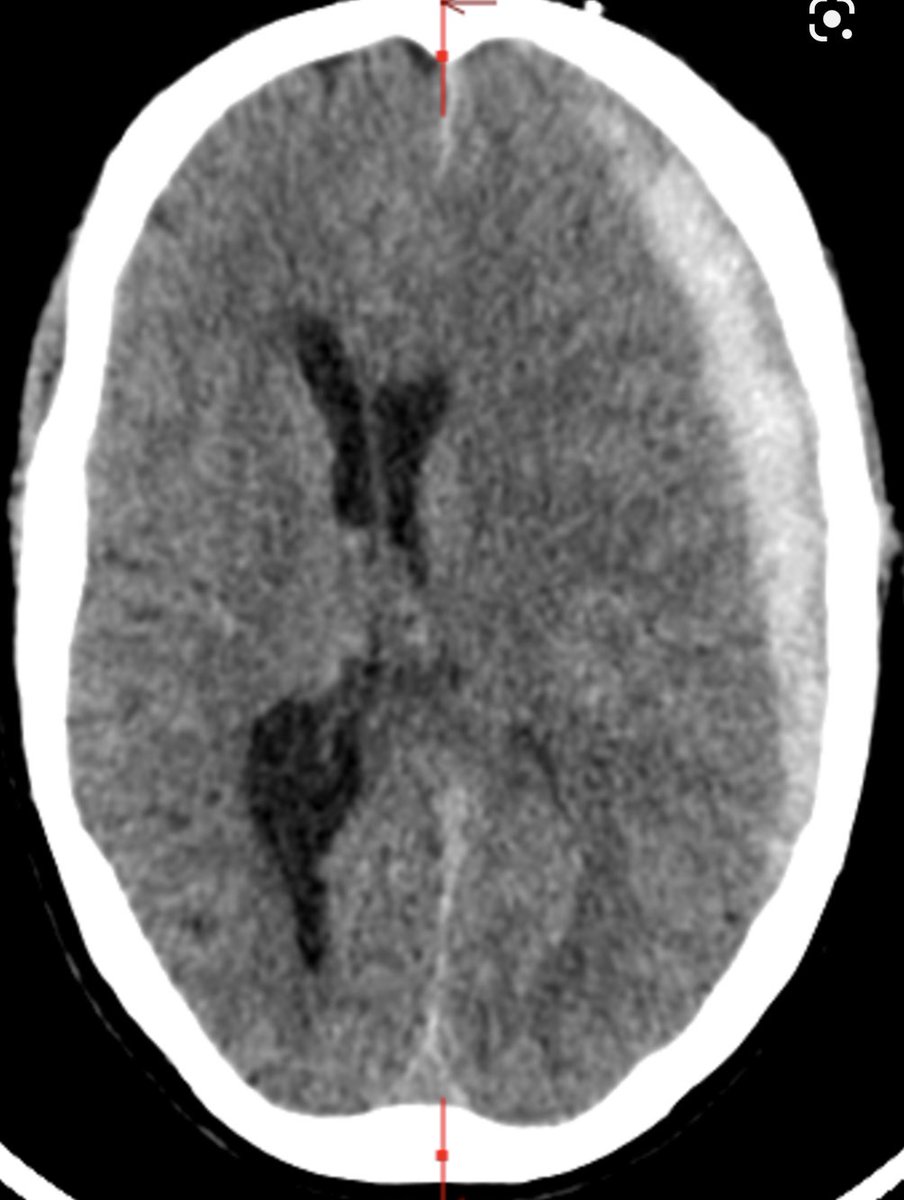

Middle aged person comes in with headache. CT (from cureus.com and for illustrative purpose only) with acute #SDH. GCS 15 and non focal exam. Patient on Xarelto. A 🧵on SDH:

Do you reverse anticoag? Last dose taken was this am.